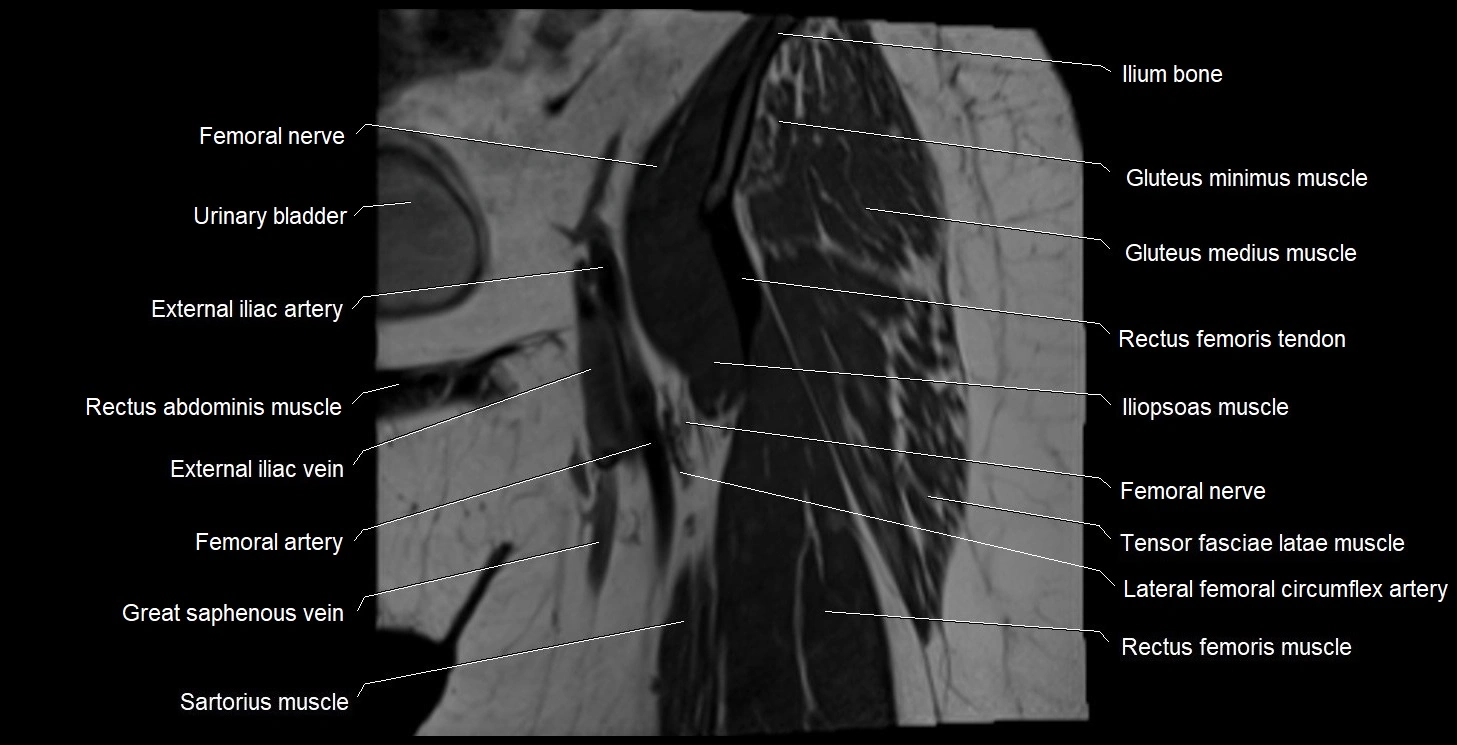

- External iliac artery

- External iliac vein

- Femoral artery

- Femoral nerve

- Femoral vein

- Gluteus maximus muscle

- Gluteus medius muscle

- Gluteus minimus muscle

- Iliopsoas muscle

- Ilium bone

- Lateral circumflex femoral artery

- Rectus femoris muscle

- Rectus femoris tendon (Proximal tendon of rectus femoris)

- Sartorius muscle

- Tensor fasciae latae muscle

- Urinary bladder

- great saphenous vein